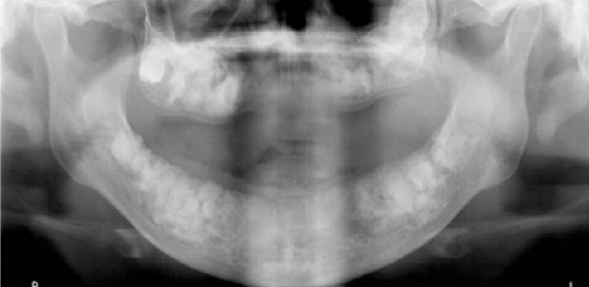

paget disease of bone

another name: osteitis deformans

a chronic metabolic bone disease

most common in men over the age of 50

pelvis and spinal column

jaws: maxilla> mandible

paget disease of bone clinical manifestations

enlargement, deformity, and pain of affected bone

jaws: spacing between the teeth, complaining of current denture

involvement of skull bones: headache, dizziness, and deafness

cotton-wool appearance

paget disease of bone radiographic features

hypercementosis

histopathologic feature of paget disease

mosaic pattern due to prominent reversal lines

paget disease of bone diagnosis

laboratory evaluation is important in establishing the diagnosis of paget disease

significant elevation of the level of serum alkaline phosphatase